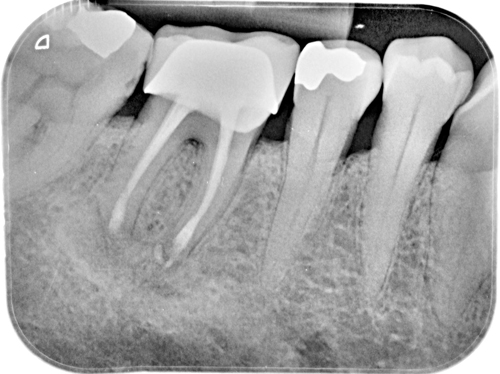

Nuestro paciente Eduardo Vicente Pedrós ha tenido en varias ocasiones infecciones en dientes que estaban desvitalizado. Él nos explica perfectamente en el vídeo que la cirugía periapical (o apicectomía) es un tratamiento que permite salvar la mayoría de los dientes afectados de esta patología.

Es una intervención técnicamente exigente, que requiere formación e instrumentos especializados (microscopio, endoscopio, etc.), pero que correctamente realizada no causa molestias prácticamente y tiene unos resultados exitosos en más del 90% de los casos.